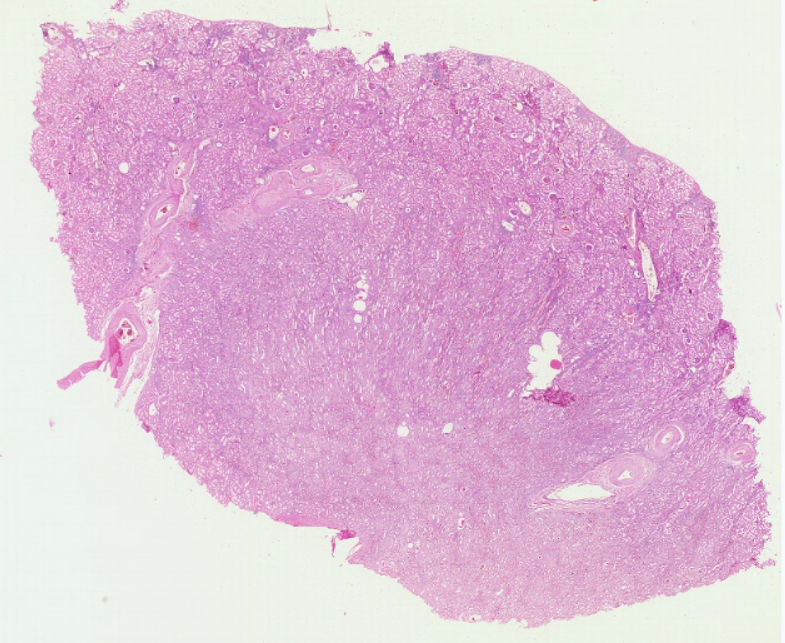

1 肾脏

低倍镜:分辨被膜、皮质和髓质。高倍镜:(1)肾小体,由血管球和肾小囊组成。肾小囊壁层为单层扁平上皮,脏层为足细胞包在血管球的表面,在切片上不容易分出。两层上皮之间为肾小囊腔。(2)近曲小管在肾小体的周围,管腔小凹凸不平不规则,管壁厚,上皮细胞较大,分界不清,核圆,位于近基底部,胞质强嗜酸性,呈深红色,游离面有刷状缘。(3)远曲小管也在肾小体的周围,与近曲小管相比,官腔相对较大而规则,上皮细胞较小,分界较清楚,核圆,位于中央或近腔面,胞质弱嗜酸性,呈浅红色,游离面无刷状缘。(4)细段在近肾乳头部易找到。细端管腔小,管壁为单层扁平上皮,但比毛细血管内皮稍厚。(5)致密斑为远曲小管靠近肾小体侧的上皮细胞形成的椭圆形斑。该上皮细胞呈高柱状,胞质色浅,核椭圆排列紧密。

全景图

2.肾小体

3.近曲小管

4.远曲小管

5.细段、集合管